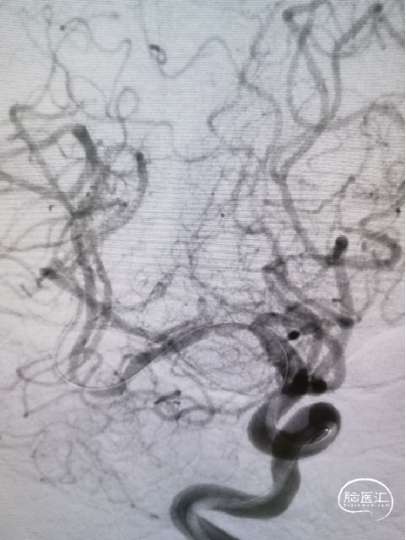

6个月复查

从6个月复查结果看到大脑中动脉穿支似乎较术前和术后即刻DSA有所减少,希望术者解释其原因并提供更多的动态影像信息,提供随访磁共振影像和临床随访结果。